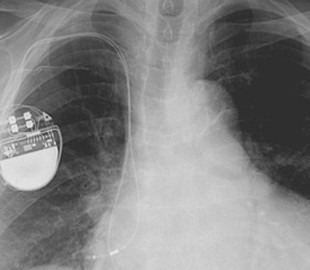

Исследователи информационной безопасности нашли способ взломать прошивку кардиостимуляторов фирмы Medtronic. Они позволяют злоумышленникам дистанционно управлять имплантами, подвергая опасности жизни их владельцев. Об этом сообщает ArsTechnica.

Уязвимость состоит в том, что прошивка не защищена цифровой подписью. При этом обновления для программистов медицинских аппаратов передаются по незащищенным каналам. Это позволяет внедрять вредоносную прошивку, способную управлять количеством ударов сердца пациента через стимулятор.